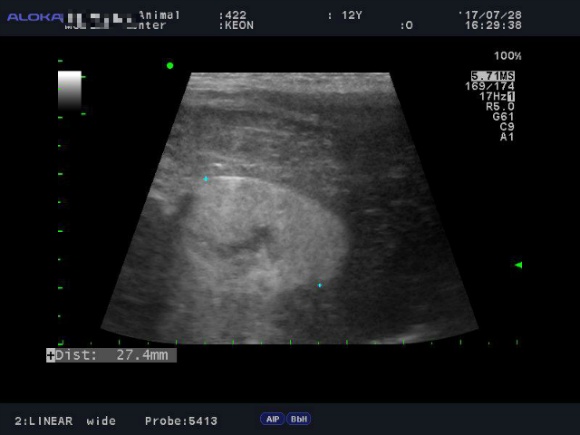

<7월28일> 다시 원점..도로아미타불입니다. 다시봐도 속상하네요 (근데 이게 담낭이 맞긴 한건가..급혼란..)

어제받은 초음파사진들은 몇장 안되니 그냥 다 올려볼게요